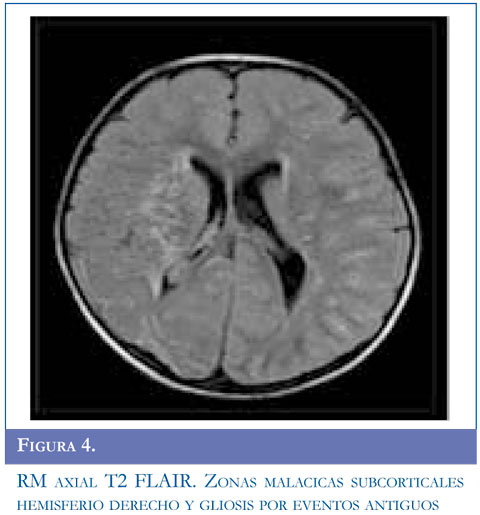

Se inició manejo con carbamazepina, se solicitó RM simple reportada con lesión sugestiva de tipo desmielinizante que compromete sustancia blanca y centros semiovales, sin realce al contraste. Ante la recurrencia de evento de hemiparesia contralateral se realizó RM de control que mostró aumento en el número de las lesiones. Se estudió enfermedad neu-rometabólica con compromiso de sustancia blanca con normalidad en ácidos orgánicos, aminoácidos en orina, acido láctico, ácidos grasos de cadena larga. Presentó nuevo evento de hemiparesia izquierda con estatus convulsivo focal se realizó TAC de cráneo que mostró ACV isquémico parietooccipital derecho, se solicitó panangiografía y doppler carotídeo. Angiografía con compromiso bilateral con hallazgos sugestivos de enfermedad de Moyamoya, y doppler trascraneal hallazgos compatibles con hipoplasia proximal de arterias cerebrales media y anterior izquierda compensado con flujo colateral a través de comunicante posterior izquierda. Valorado por neurocirugía no consideraron manejo quirúrgico. El paciente ha continuado presentando episodios transitorios de ACV. Figuras 4, 5 y 6

Para el estudio de esta enfermedad ante la sospecha clínica se deben solicitar estudios radiológicos como tomografía computarizada de cráneo (TAC) evidenciando áreas pequeñas de hipodensidad que sugieren hemorragia o isquemia en región cortical, ganglio basal, profundidad de sustancia blanca o región periventricular; sin embargo, la TAC puede ser normal si el paciente presenta un evento isquémico transitorio. En todos los pacientes de esta serie, se solicitó TAC encontrandose lesión focal secundaria al evento vascular en regiones subcorticales y gangliobasales. La disponibilidad de RM y angiografía por RM se ha convertido en el método diagnóstico del síndrome de Moyamoya. Un infarto cerebral agudo es más probable que se detecte con el uso de imagen por difusión, un infarto cerebral crónico se observa en RM en T1-T2. El flujo sanguíneo cortical disminuido se observa en la secuencia FLAIR como una señal lineal intensa que sigue la forma de los surcos llamado "signo de la hiedra" (14). Los hallazgos más frecuentes en RM son reducción del flujo de la arteria carótida interna, arteria cerebral anterior y media hasta llegar a ausencia de flujo sanguíneo en ganglios basales y tálamo con formación de vasos colaterales; en este informe el examen confirmatorio se realizó con angiografía, se debe realizar estudio de 5 o 6 vasos que incluyan arterias carótidas externas, carótidas internas y 1 ó 2 arterias vertebrales según colaterales que se presenten. El diagnóstico definitivo se basa en el aspecto arteriográfico caracterizado por estenosis de la arteria carótida interna a nivel distal, extendiéndose a la región proximal y media (15). La severidad de la enfermedad se clasifica de I a VI estadios de progresión según el sistema de clasificación de Suzuky (16) (Tabla 1). En los casos presentados el grado de estatificación fue IV y V mientras que en la serie de González (5) existieron varias presentaciones I, III y VI; Galicchio (6) presentó casos en estadio II a III.